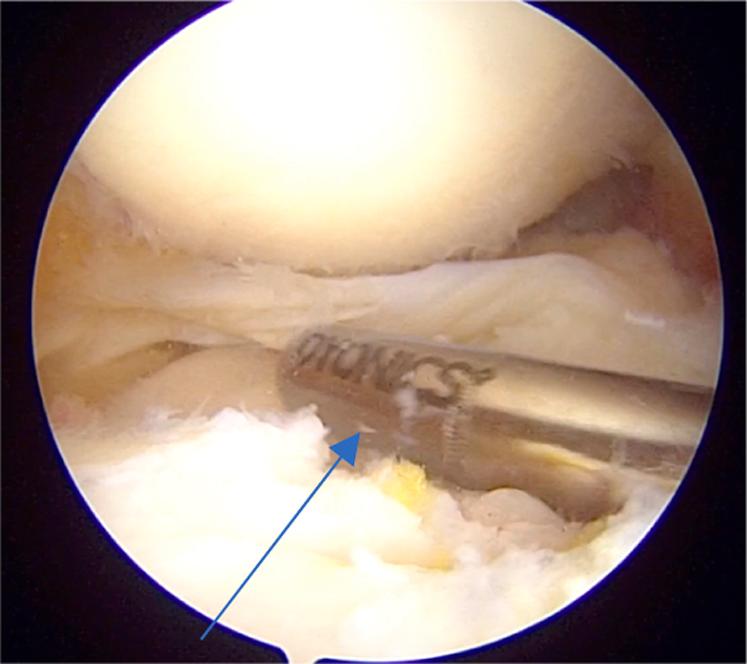

The meniscus plays a very important role in normal functioning of the knee joint. It acts as a shock absorber, gives stability to the knee joint, delays the onset of osteoarthritis, provides load sharing, and so on. It is a well-known fact that after meniscectomy, there is a significant increase in joint reaction forces leading to early osteoarthritis. Hence, in the past decade, meniscal repair has gain enormous importance and various techniques have been developed to repair the meniscus. Conventionally, posterior-third meniscal tears are repaired with all-inside and outside-in techniques whereas middle-third meniscal tears are repaired with all 3 methods: inside out, outside in, and all inside. For tears of the anterior horn of the meniscus, only the outside-in method is used. We have developed a method for repair of chronic unreduced, retracted bucket-handle anterior horn lateral meniscal tears, in which we combined the use of both the outside-in and all-inside methods of repair. Hence, this method is called modified outside-in meniscal repair for chronic retracted bucket-handle anterior horn lateral meniscal tears.

半月板在膝关节的正常功能中起着非常重要的作用。它充当减震器,为膝关节提供稳定性,延缓骨关节炎的发生,分担负荷等等。众所周知,半月板切除术后,关节反应力会显著增加,导致早期骨关节炎。因此,在过去十年中,半月板修复变得极其重要,并且已经开发出各种技术来修复半月板。传统上,后三分之一半月板撕裂采用全关节内和由外向内技术修复,而中三分之一半月板撕裂则采用三种方法修复:由内向外、由外向内和全关节内。对于半月板前角的撕裂,仅使用由外向内方法。我们已经开发出一种修复慢性未复位、回缩的桶柄状前角外侧半月板撕裂的方法,在该方法中,我们结合使用了由外向内和全关节内两种修复方法。因此,这种方法被称为用于慢性回缩桶柄状前角外侧半月板撕裂的改良由外向内半月板修复术。